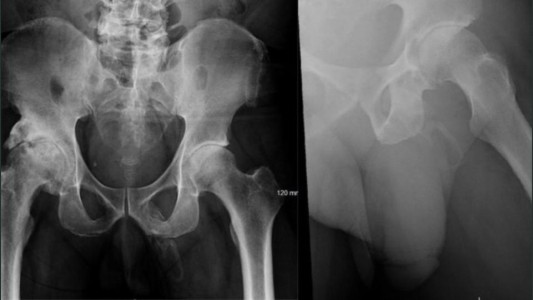

Sufrió quemaduras por una descarga eléctrica que pasó del cargador de su celular al collar que llevaba puesto